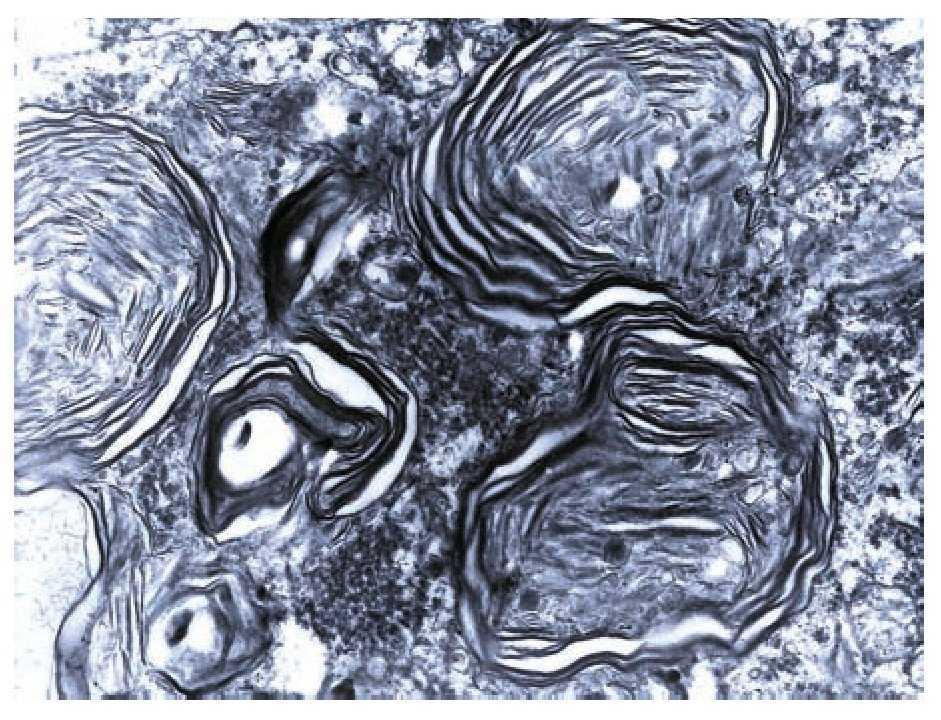

A complete autopsy was performed. Weight and height were within normal limits. On external examination, both coarse face and depressed nasal bridge were identified. In situ inspection of the pelvic organs was unremarkable. The lungs showed gross changes consistent with pneumonia. Hepatosplenomegaly was present. The brain weighed 831 g (normal weight according to age/height: 691 g). The most significant gross finding on autopsy was the presence of enlarged convolutions of the frontal and parietal cerebral cortex; sulci also appeared short and scanty (Figure 1). These features were more evident on cut surface. The ventricular system, the brain stem, and the cerebellum showed no abnormalities. Except for the eyes, routine representative sections of the organs were submitted for histology. The initial histopathological study demonstrated bilateral acute pneumonia as the direct cause of death. Sections from the central nervous system (CNS), the spinal cord, and sympathetic ganglia from the paravertebral region showed that neurons presented severe morphological changes. The most striking degenerative changes consisted in neuronal enlargement with broad dendritic processes lacking slender cellular borders. The normal appearance of the cytoplasm was replaced by a large amount of granular material leading to swollen neurons with displaced nuclei (Figure 2); the intracytoplasmic material was positive for periodic acid-Schiff stain with diastase digestion and luxol fast blue. In addition, both astrogliosis in the brain cortex and spinal cord and ectopic neurons in the cerebellum were seen. Similar cytoplasmic changes were identified in interalveolar and gastrointestinal macrophages. The thymus, the spleen, the liver, and the heart were also affected. Tissue from the CNS and the lungs was submitted for electron microscopy. Ultrastructural study demonstrated numerous whorled membranous and stacked intracytoplasmic structures (Figure 3), which represent massive accumulation of glycolipids. Through histological and ultrastructural findings besides the clinical picture, the diagnosis of a lysosomal storage disease affecting the CNS and viscera consistent with infantile generalized gangliosidosis was made.

Figure 3. Numerous membranous lamellar bodies are seen in this Ultrastructure.